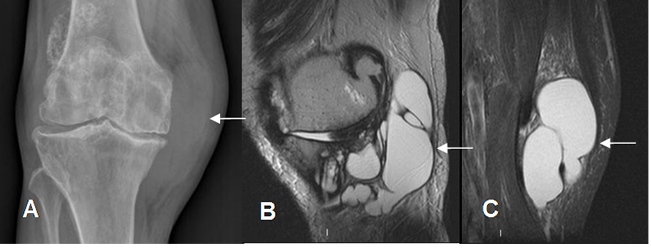

- A: Rx AP. Prominencia de los tejidos blandos en la parte medial de la rodilla.

- B: RM sagital en T2 y C: RM coronal en STIR. Imágenes quísticas que desplazan los tendones de la pata de ganso, por bursitis.